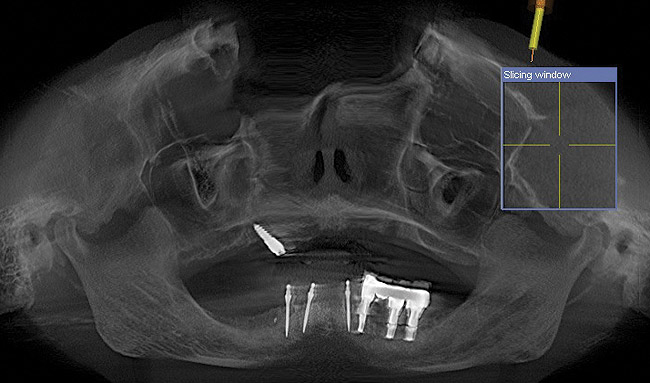

The patient was scanned with a cone beam CT scan while wearing a radiopaque scanning appliance based on her new treatment denture. Horizontal bone augmentation was confirmed radiographically, and both grafted sinuses resulted in satisfactory bone quantity for implant placement. Vertical augmentation was not attempted because of the patient’s unwillingness to forego her removable prosthesis for any period of time. Therefore, shorter implants were treatment-planned, resulting in the placement of eight implants, rather than fewer—such as six—implants, to support a full-arch fixed prosthesis. Because adequate bone and keratinized mucosa were present, a flapless, computer-guided implant insertion was performed (Figure 18). After removal of the surgical guide, placement of all eight implants could be inspected (Figure 19). Post-placement periapical radiographs are shown in Figure 20 and Figure 21.

Figure 18  Flapless, computer-guided implant insertion.

Figure 18

Figure 24  Postoperative CT scan demonstrated horizontal bone regeneration.

Figure 24

Figure 25  Postoperative CT scan demonstrated horizontal bone regeneration.